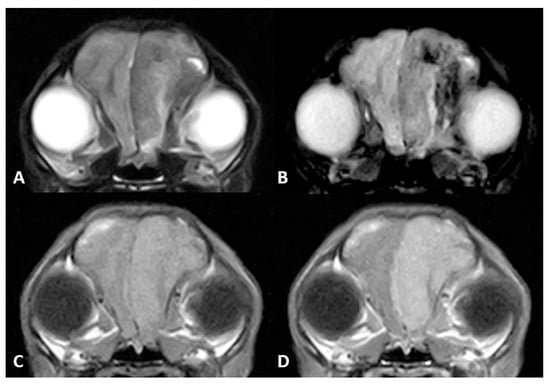

A routine MR imaging study was performed with T1w, T2w, fluid attenuation inversion recovery (FLAIR), postcontrast T1 (T1w+c), gradient echo (T2*) transverse sequences (see Figure 1), and T2w, T1w and T1w+c sagittal sequences.

Diffuse thickening of the meninges covering the left hemisphere was seen. A plaquelike lesion extending from the left olfactory bulb involving the meninges along the convexity of the whole hemisphere, extending to the falx cerebri and affecting partially the adjacent right cerebral hemisphere, was observed. The mass was markedly hypointense with respect to grey matter on T2w, FLAIR and T2* sequences, isointense on T1w with focal areas of hyperintensity, and showed marked and uniform enhancement after contrast administration. Adjacent to this lesion, mild diffuse T2w and FLAIR hyperintensity was present affecting the brain parenchyma. The lesion was causing a severe mass effect over the left lateral ventricle and subfalcine brain herniation of the left cerebral hemisphere. The cerebral sulci of the affected side were moderately attenuated, suggesting increased intracranial pressure.

Figure 1. Magnetic resonance (MR) imaging of the brain of Case 1, transverse images at the level of the thalamus. A plaquelike extra-axial mass is visible covering the left hemisphere with (A) a marked hypointense signal on T2-weighted (T2w) sequences and (B) fluid attenuation inversion recovery (FLAIR). (C) T1-weighted (T1w) hyperintensity was not visible, but (D) marked enhancement after contrast administration could be detected. Note the severe mass effect and peritumoral oedema causing occlusion of the left lateral ventricle.